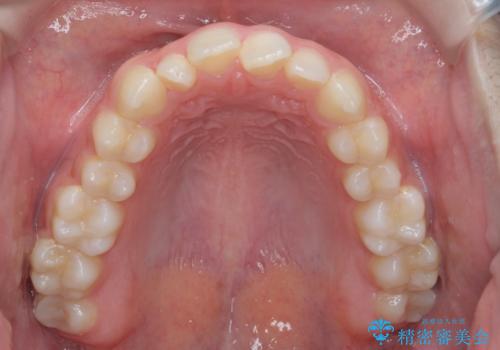

前歯のガタつき・ねじれを治すマウスピース矯正

- 前歯のねじれ、ガタつきを改善し綺麗な歯並びにしたいと希望され来院されました。

マウスピース矯正インビザラインによる矯正治療を計画しますが、マウスピース矯正で治りにくい歯のねじれを事前にワイヤー矯正でしっかりとなおしておくことで矯正治療期間の短縮できるような治療計画を立てます。

マウスピース矯正を始める前にワイヤー部分矯正を行ったことで改善のしにくい歯のねじれをしっかりと治すことができました。